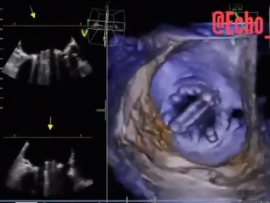

Lee masParavalvular Leakage at 3 o’clock of Mitral Valve. Mohammed Zidan, MBBCH, M.Sc Cardiology (Cardiology, Echocardiography and interventional Cardilogy Specialist at Al-Azhar university), Cairo, Egypt.